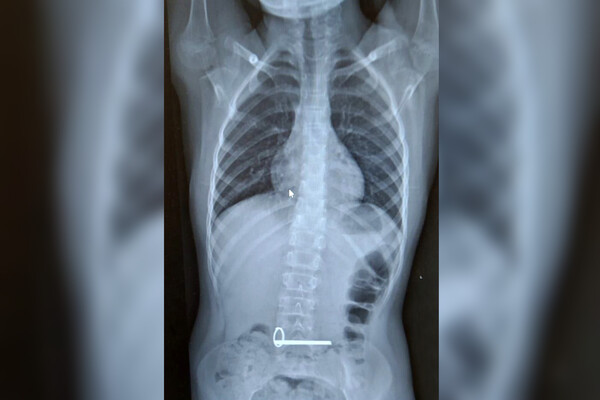

Школьник поступил в отделение экстренной помощи с подозрением на инородное тело в желудке. В ходе обследования было установлено, что мальчик проглотил два металлических ключа.

Эндоскописты извлекли ключи без каких-либо осложнений для ребенка, манипуляцию провели под наркозом. Жизни и здоровью несовершеннолетнего ничто не угрожает.